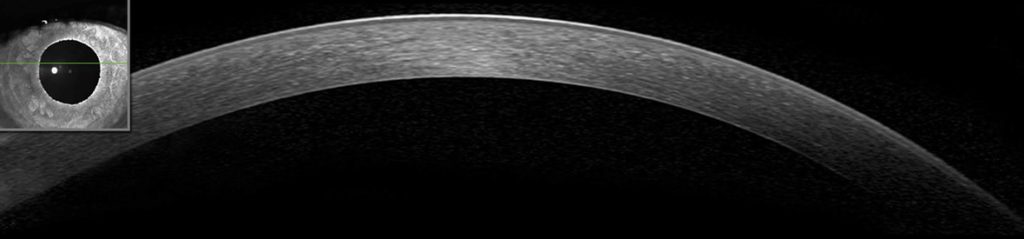

6.Módulo do Segmento Anterior

Imagens de Alta Resolução do Segmento Anterior

As imagens de alta resolução obtidas com o Módulo do Segmento Anterior SPECTRALIS® mostram as camadas da córnea em detalhes e auxiliam na avaliação da espessura corneana. O módulo também oferece imagens de ângulo a ângulo para uma avaliação eficiente do ângulo da câmara anterior, bem como imagens detalhadas das estruturas da esclera.

• Cornea

• Anterior Chamber Angle

• Sclera